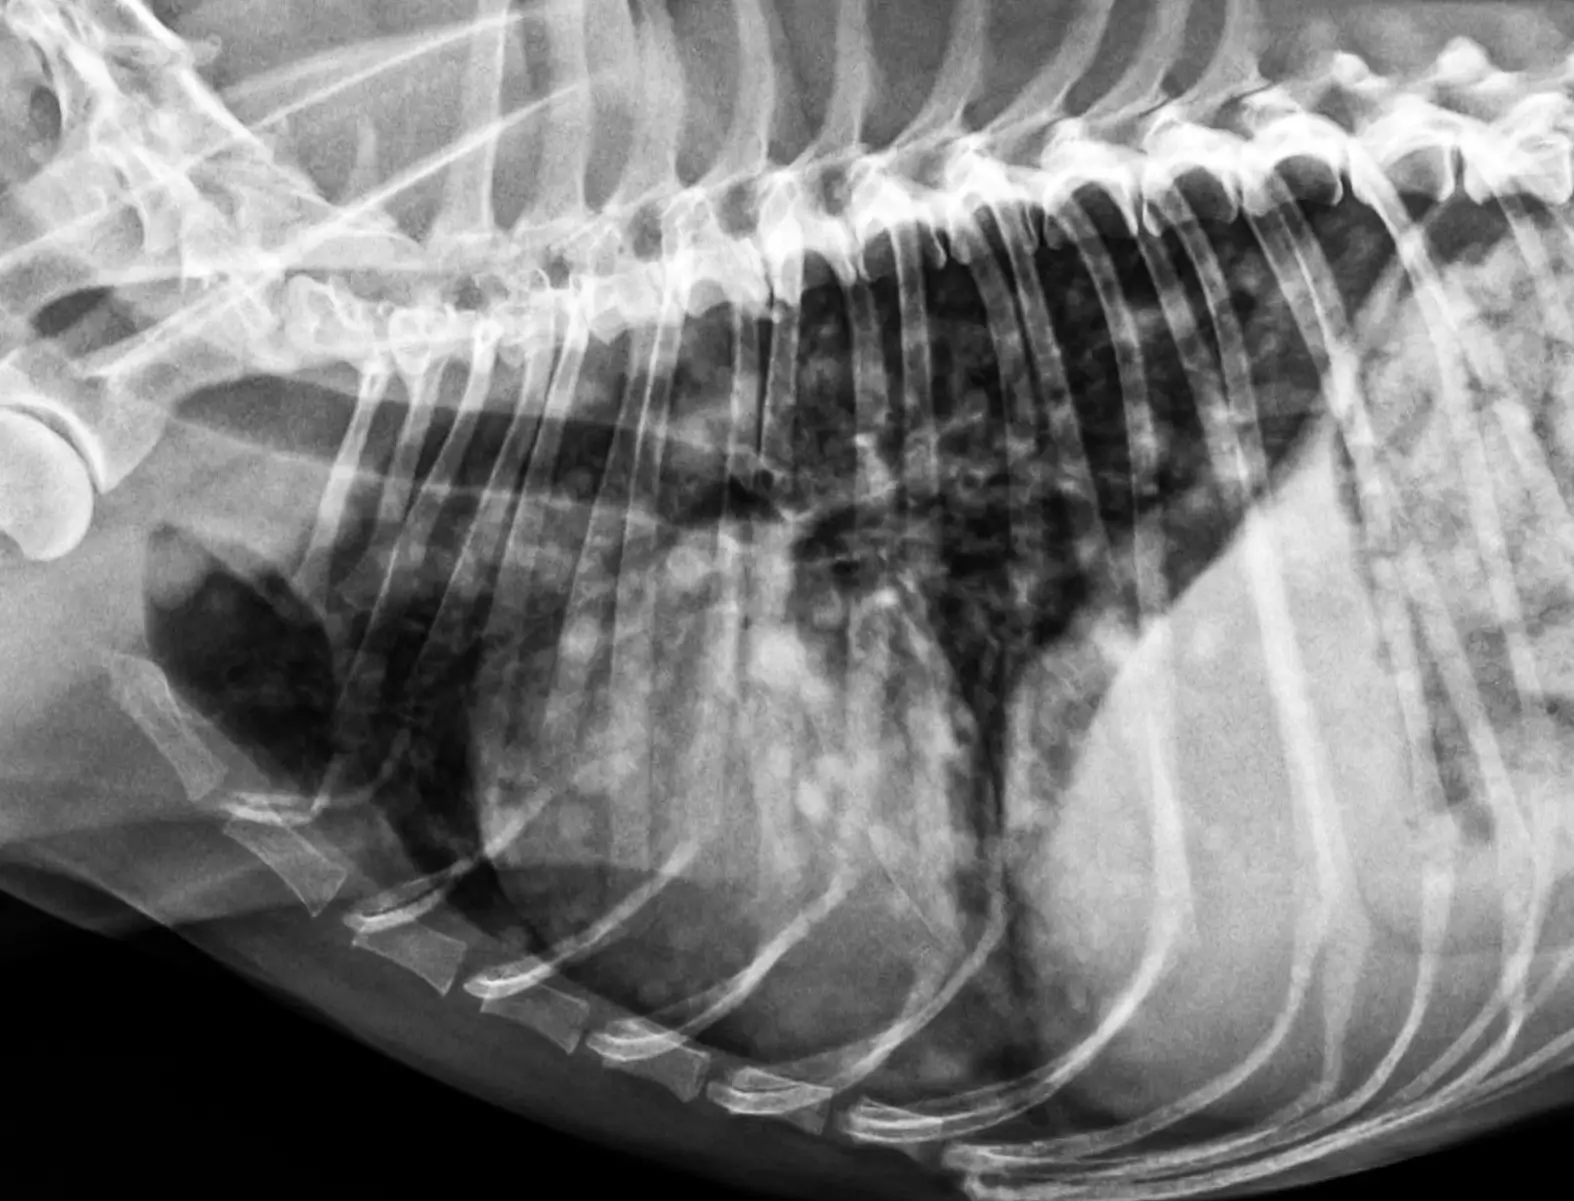

- 正確な検査:病理医による細胞診/病理組織検査・Bone Suppression処理による精度の高いレントゲン検査、

ご家族さまにも分かりやすい画像やビデオ記録を行っています。